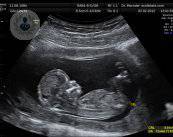

• ecografia-embarazo-diagnostico-prenatal

Diagnóstico Prenatal: esencial para la salud del bebé y la madre

¿Estás embarazada? ¿Sabías que el Diagnóstico Prenatal es muy importante para tu salud y la de tu bebé? La Dra. de Paco, experta en Ginecología y Obstetricia, te informa